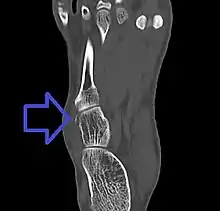

Avulsion fracture of the cuboid on CT

A cuboid fracture is a fracture of the cuboid bone of the foot. Diagnosis is by X-ray imaging, magnetic resonance imaging, or bone scan.[1] Treatment may be conservative or involve surgery, depending on the type of fracture.[1] They are rare.[1]

If the cuboid bone is broken, then it is common for other bones in the foot to be broken or dislocated as well.[2] Cuboid fractures are associated with Lisfranc injuries.[2]